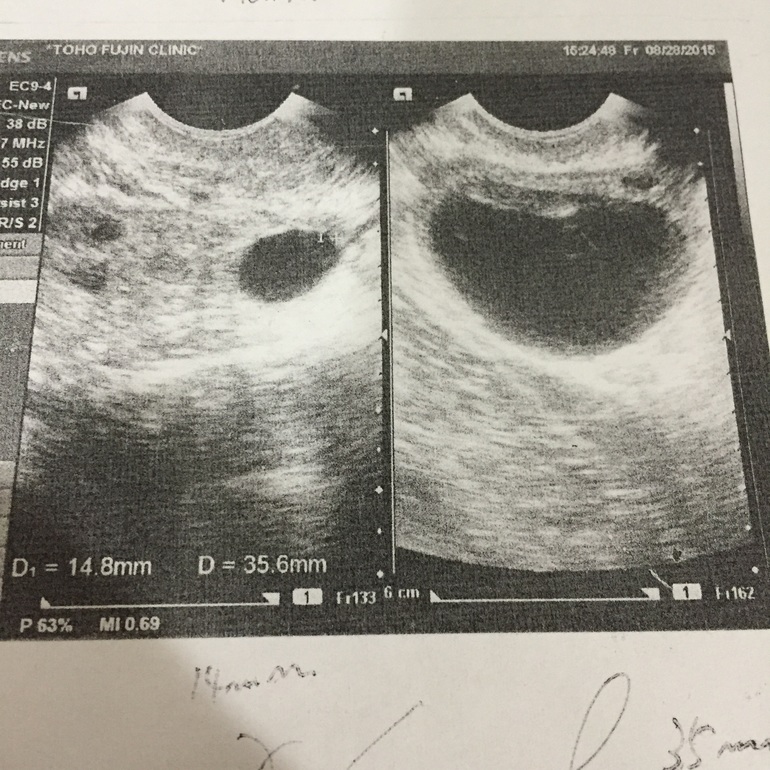

Гинекологические заболеванияПосле выкидыша 12-го числа этого месяца мне делают фолликулометрию, по инициативе врача. Так вот, сегодня в ЛЯ фолликул 35, 6! Огромный! У меня все болит, сидеть не могу(( в ПЯ 14,8мм. Ровно неделю назад в левом вообще ничего не было! Сэнсэй говорит, что мол плохой это Ф. Я спрашиваю киста? Нет говорит, киста после 40мм. Ничего толком не объясняет, я ваще ничего не понимаю что происходит. Из-за гормонального сбоя нет овуляции? Ф не может разорваться? Тесты на овуляцию начали показывать слабую полоску, сегодня была более менее ярка, но недостаточно, сто означает отр результат.

Взяли анализ на гормоны (эстрадиол, пролактин, ЛГ, ФСГ) и отправили домой .